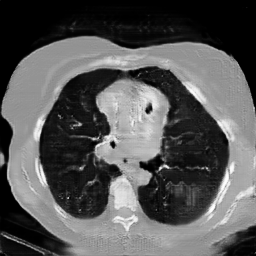

The study utilizes three 3D datasets, namely the GSP dataset[3], the LIDC-IDRI dataset[1], and the dataset employed for the Lung Nodule Analysis 2016 (LUNA16) challenge[21] which is a subset of LIDC-IDRI dataset. Samples from generated images at different stages of training are presented in Fig. 2 and Fig.3.

CRF-GAN synthetic images at different iterations

Refer to caption

20000

30000

40000

50000

60000

70000

80000

HA-GAN synthetic images at different iterations

Figure 2: Synthetic images of CRF-GAN and HA-GAN at different iterations of training on GSP dataset